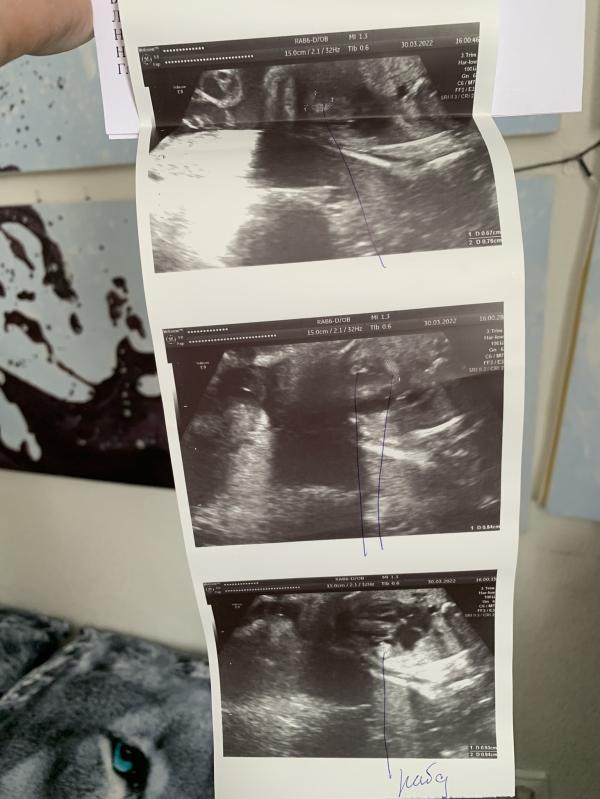

Наступило время ехать на Флотскую. Меня сразу отправили на узи, чтобы врачи убедились во всём сами. Ну и конечно же, эти чёртовы опухоли никуда не делись😭

Для того, чтобы точно подтвердился Туберозный склероз, на узи начали искать опухоли в голове у малыша. Их не нашли🙏

Но тут не понятно, либо их там действительно нет, либо по узи просто их не заметили. Тут поможет только МРТ плода, но на МРТ меня почему-то не отправили.